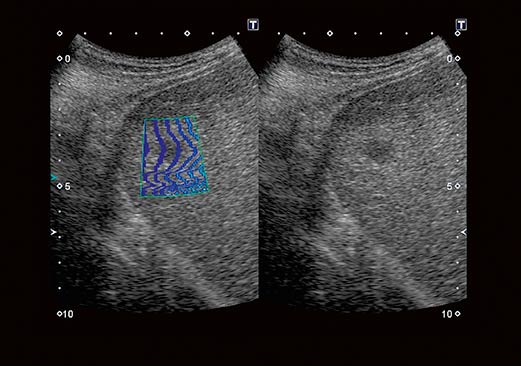

Технология Advanced Dynamic FlowTM (ADF) обеспечивает высочайшее пространственное разрешение в режиме цветового допплеровского картирования, позволяя с высокой точностью и детализацией выявлять мелкие сосуды и зоны со сложным характером кровотока, в полной мере сохраняя качество изображений, присущее B-режиму.

Цветовая энергетическая ангиография сочетает чувствительность и глубину проникновения энергетического допплера с информацией о направлении кровотока, полученной при цветовом допплеровском картировании, позволяя более точно определять сосудистый рисунок ткани.

Технология визуализации микроциркуляторного русла (SMI), разработанная корпорацией Canon Medical Systems, расширяет диагностические возможности ультразвуковых систем Aplio. Позволяет визуализировать низкоскоростной кровоток в микрососудах.